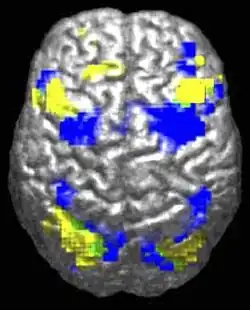

Neuroanatomical studies support that autism may involve abnormal neuronal growth and pruning, leading to brain enlargement in some areas and reduction in others.[13] Functional neuroimaging studies show reduced activation in somatosensory cortices during theory of mind tasks in autistic individuals and highlight potential imbalances in neurotransmitters like glutamate and Γ-aminobutyric acid that may underlie autism's behavioral manifestations.[14]

The underconnectivity theory of autism posits that autistic people tend to have fewer high-level neural connections and less global synchronization, along with an excess of low-level processes.[31] Functional connectivity studies have found both hypo- and hyperconnectivity in brains of autistic people.[32] Hypoconnectivity is commonly observed for interhemispheric (e.g. lower neuron density in corpus callosum)[33] and cortico-cortical functional connectivity.[34] Some studies have found local overconnectivity in the cerebral cortex and weak functional connections between the frontal lobe and the rest of the cortex.[35] Abnormal default mode network (task-negative) connectivity is often observed. Toggling between task-negative network activation and task-positive network activation (consisting of the dorsal attention network and salience network) may be less efficient, possibly reflecting a disturbance of self-referential thought.[36] Such patterns of low function and aberrant activation in the brain may depend on whether the brain is performing social or nonsocial tasks.[37]